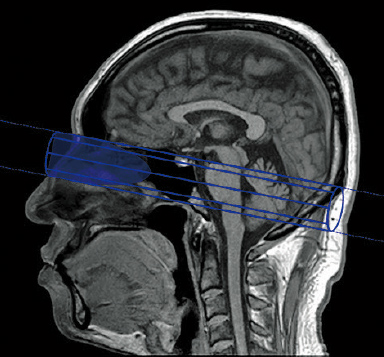

AutoPose*1

Skanogram işlevi, bilgilerin operatörler için bölgelerin kesit alanlarında hızlı bir şekilde görüntülenmesini sağlar.